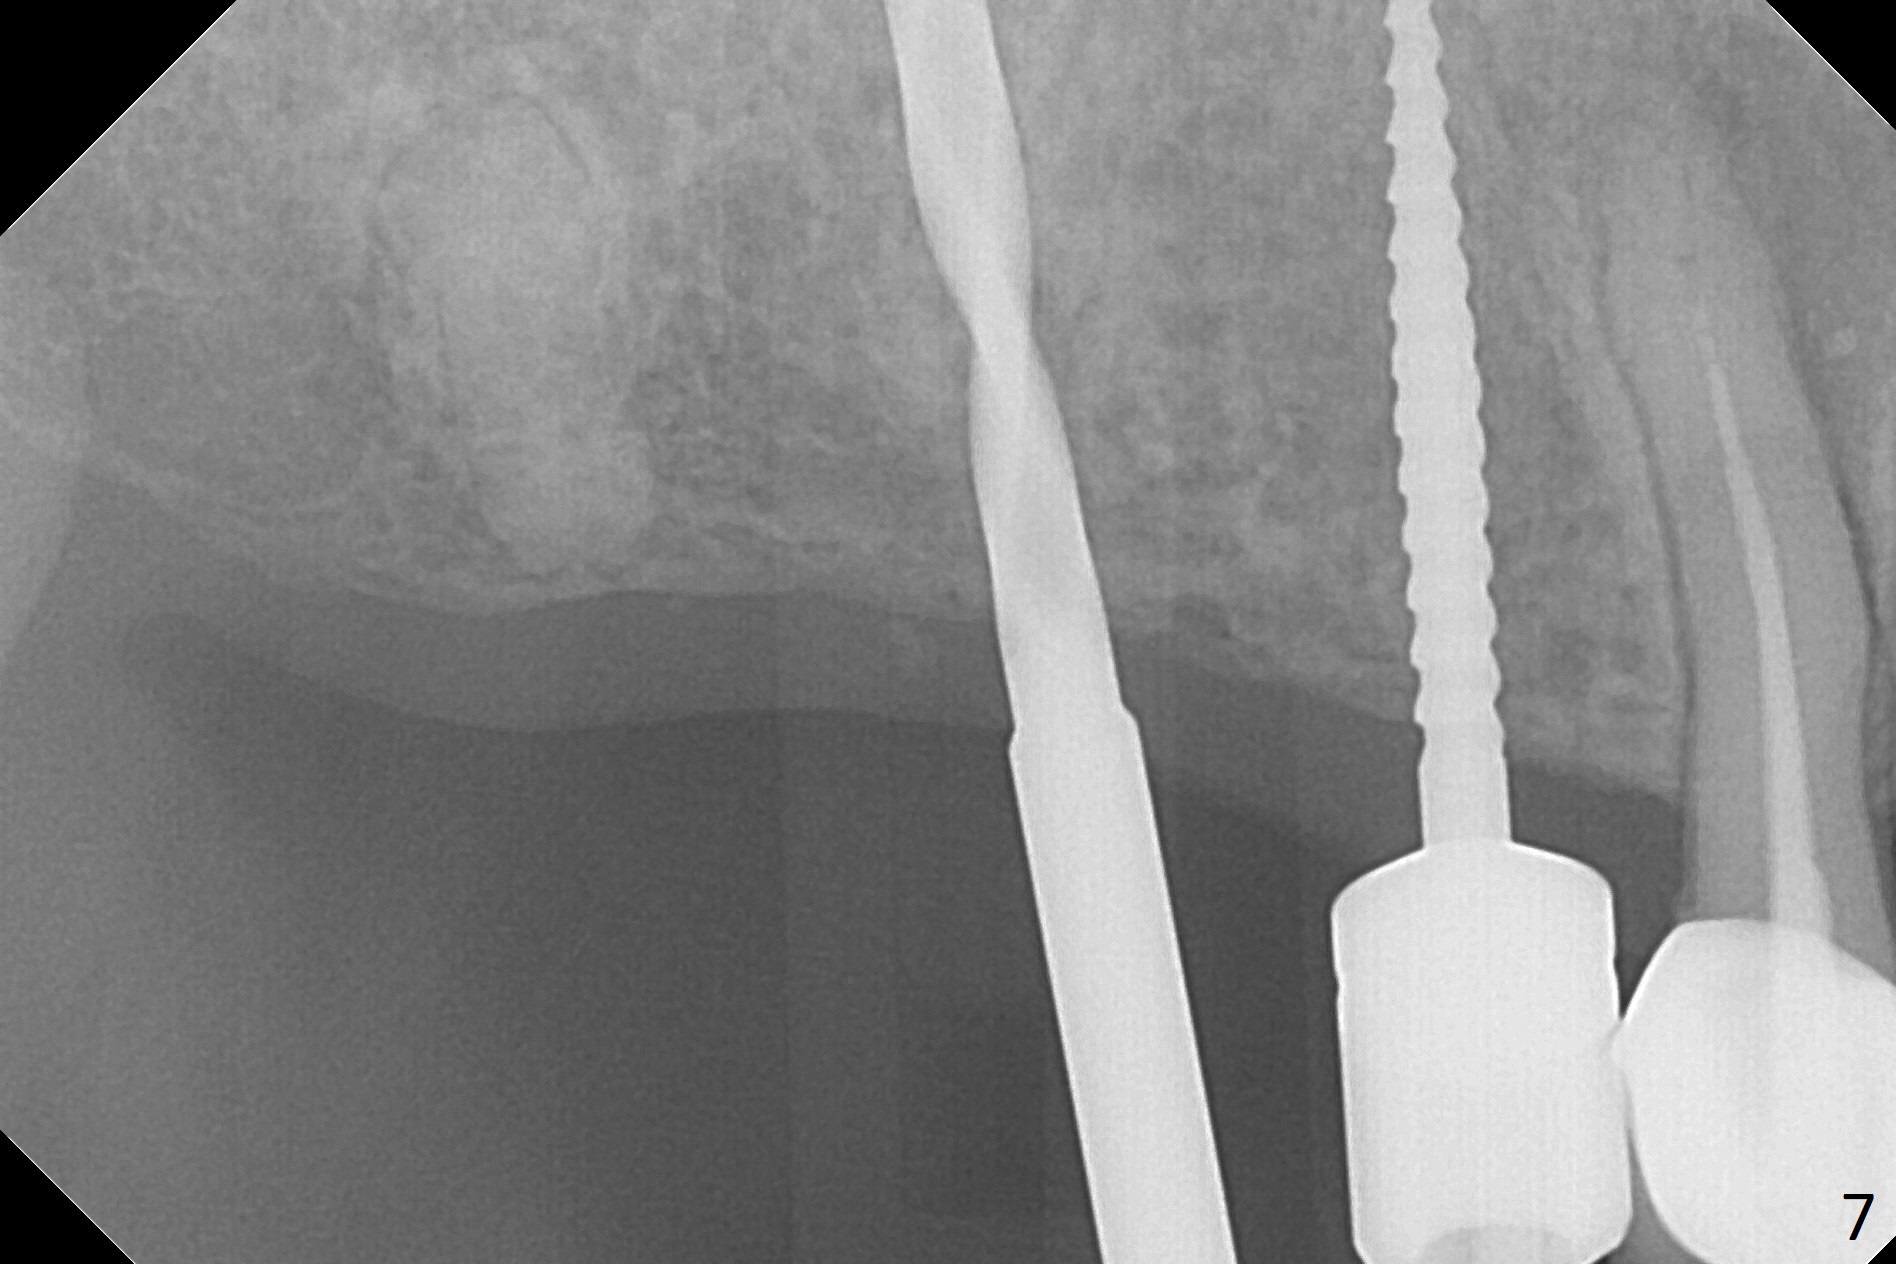

The ridge at #3,4 is wide (Fig.1). A surgical stent is placed (Fig.2) for initial osteotomy (Fig.3). When the stent is removed, the osteotomies need to move palatal (Fig.4 arrows). As two of 1.2 mm drills are in place (Fig.5), mesiodistal trajectories are found off (Fig.6). After the trajectories are corrected (Fig.7), the depth cannot be determined with PA (Fig.8, as compared to Pan (Fig.9)). Following 4.3 and 3.2 mm final drills at #3 and 4, 4.5x13 and 3.8x15 mm implants are placed with insertion torque of 35 and 50 Ncm, followed by 5.5x4(3) and 4.5x4(2) mm abutments (Fig.10). BWs show incomplete placement of the implant at #4 distal (Fig.11,12). Later the implant is placed ~ .5 mm deeper. Periodontal dressing is applied postop. CT-assisted surgical guide must be more efficient for this case with wide ridge. There is no bone loss around the implants 3 moths postop